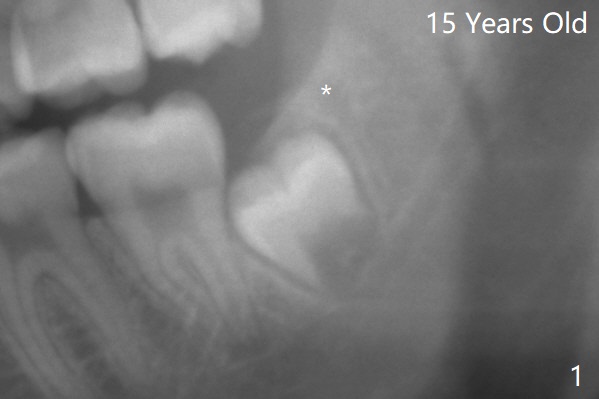

18岁时三角形变大,密度增高(图二)。其实术中发现外斜嵴两侧都不明显(女孩原因?),拔除两侧都需要颊侧去骨。由于左侧智齿颊侧阻生(图三:*),拔除后两侧都放置骨水泥(Bond Apatite,图四:A)促进骨修复,口腔卫生欠缺,可能容易形成牙周炎。